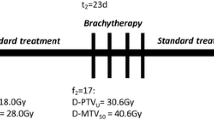

Cervical cancer is the fourth most common malignancy in women and also the fourth most common cause of death from cancer in women worldwide (Sung et al. 2021). For locally advanced diseases, concomitant Cisplatin-based chemoradiation therapy is considered the standard of care with a brachytherapy boost to the local disease (Green et al. 2001; Hsu et al. 2015; Shrivastava et al. 2018). Additionally, an external beam radiotherapy (EBRT) boost should be given to nodal volumes in patients with lymph node (LN) involvement (Bacorro et al. 2018; Wujanto et al. 2019; Kim et al. 2020). Administration of this boost dose to involved LNs is associated with increased normal tissue toxicity because of a larger irradiated volume exposed to higher radiotherapy (RT) doses. This toxicity is further augmented due to the use of concomitant chemotherapy during RT. Therefore, an intensity-modulated technique such as Volumetric Intensity Modulated Arc therapy (VMAT) is favored as it allows for dose intensification while mitigating normal tissue toxicity (Gaffney et al. 2011; Knapp et al. 2019). There are two possible ways of nodal boost during EBRT: Sequential (SEQ) or Simultaneous Integrated Boost (SIB). A sequential boost can be delivered to gross nodes which allows dose intensification with low treatment-related toxicities (Shewalkar et al. 2022). This modality was always considered to be an acceptable option keeping in mind the concern for normal tissue tolerance. Nevertheless, SEQ-RT increases the total treatment time, particularly if a boost is delivered before brachytherapy which could potentially worsen local tumour control (Tanderup et al. 2016; Lin et al. 2017; Hong et al. 2017). On the other hand, the non-homogeneous irradiation of the tumour and lymph nodes to different doses with SIB delivers the initial and boost doses together in a smaller number of fractions and, thus, in a shorter overall treatment time (OTT). However, SIB with increased dose per fraction to involved LN raises theoretical concerns of amplified toxicity (Jensen et al. 2021). Thus, a comprehensive analysis of these two techniques taking into account dosimetric and radiobiological considerations could provide true insight.

For the SIB plans, the prescribed dose was 50.4 Gy to the pelvis (primary tumour, uterus, and the parametrium and elective nodal volume) and 58.8 Gy to the FDG-avid nodes. These doses were delivered in 28 fractions over 5.6 weeks. For the SEQ-VMAT plans, the prescribed dose was 50.4 Gy to the pelvis in 28 fractions (primary tumour, uterus, and the parametrium) followed by a boost of 9 Gy in five fractions to the involved LN. Plans were optimized to achieve adequate target coverage with maximal sparing of the OARs.

The main limitation of the present study is the retrospective design with a relatively small number of patients. Data regarding brachytherapy were not included in the analysis as simply combining the results of both brachytherapy and VMAT was considered scientifically inappropriate. Radiobiologically both these treatment modalities are entirely different and simple dose addition is unjustifiable.